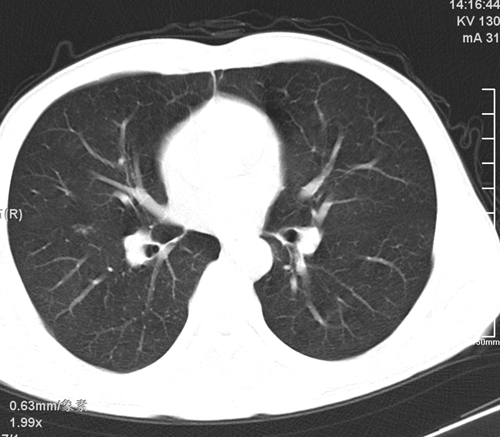

标题: CT24548:男 31 咳嗽 咯血一天 行CT检查 [打印本页]

标题: CT24548:男 31 咳嗽 咯血一天 行CT检查

ct考虑结核 但化验结果示白细胞总数 淋巴均正常,血沉7mm/h不快,请看看结核 支扩还是其他

考虑右肺继发性肺结核伴空洞形成。

右肺继发性肺结核伴右肺下叶背段空洞形成。

继发性肺结核伴空洞形成